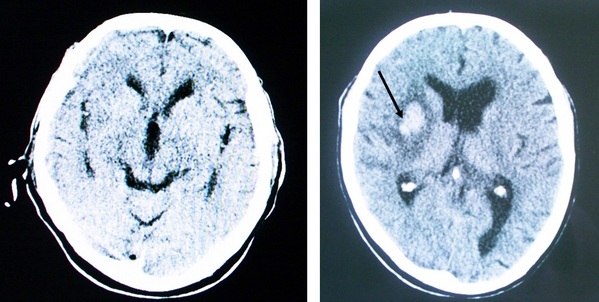

Диагностические мероприятия

Сначала доктор изучает жалобы и анамнез заболевания, затем проводит физикальное обследование, оценивает неврологический статус, исключает внечерепные причины патологии.

Потом назначается лабораторная и инструментальная диагностика:

- Анализы крови, мочи.

- КТ и МРТ головного мозга.

- Рентгенография грудной клетки.

- Электрокардиография.

Это помогает определить тип патологии, ее обширность.